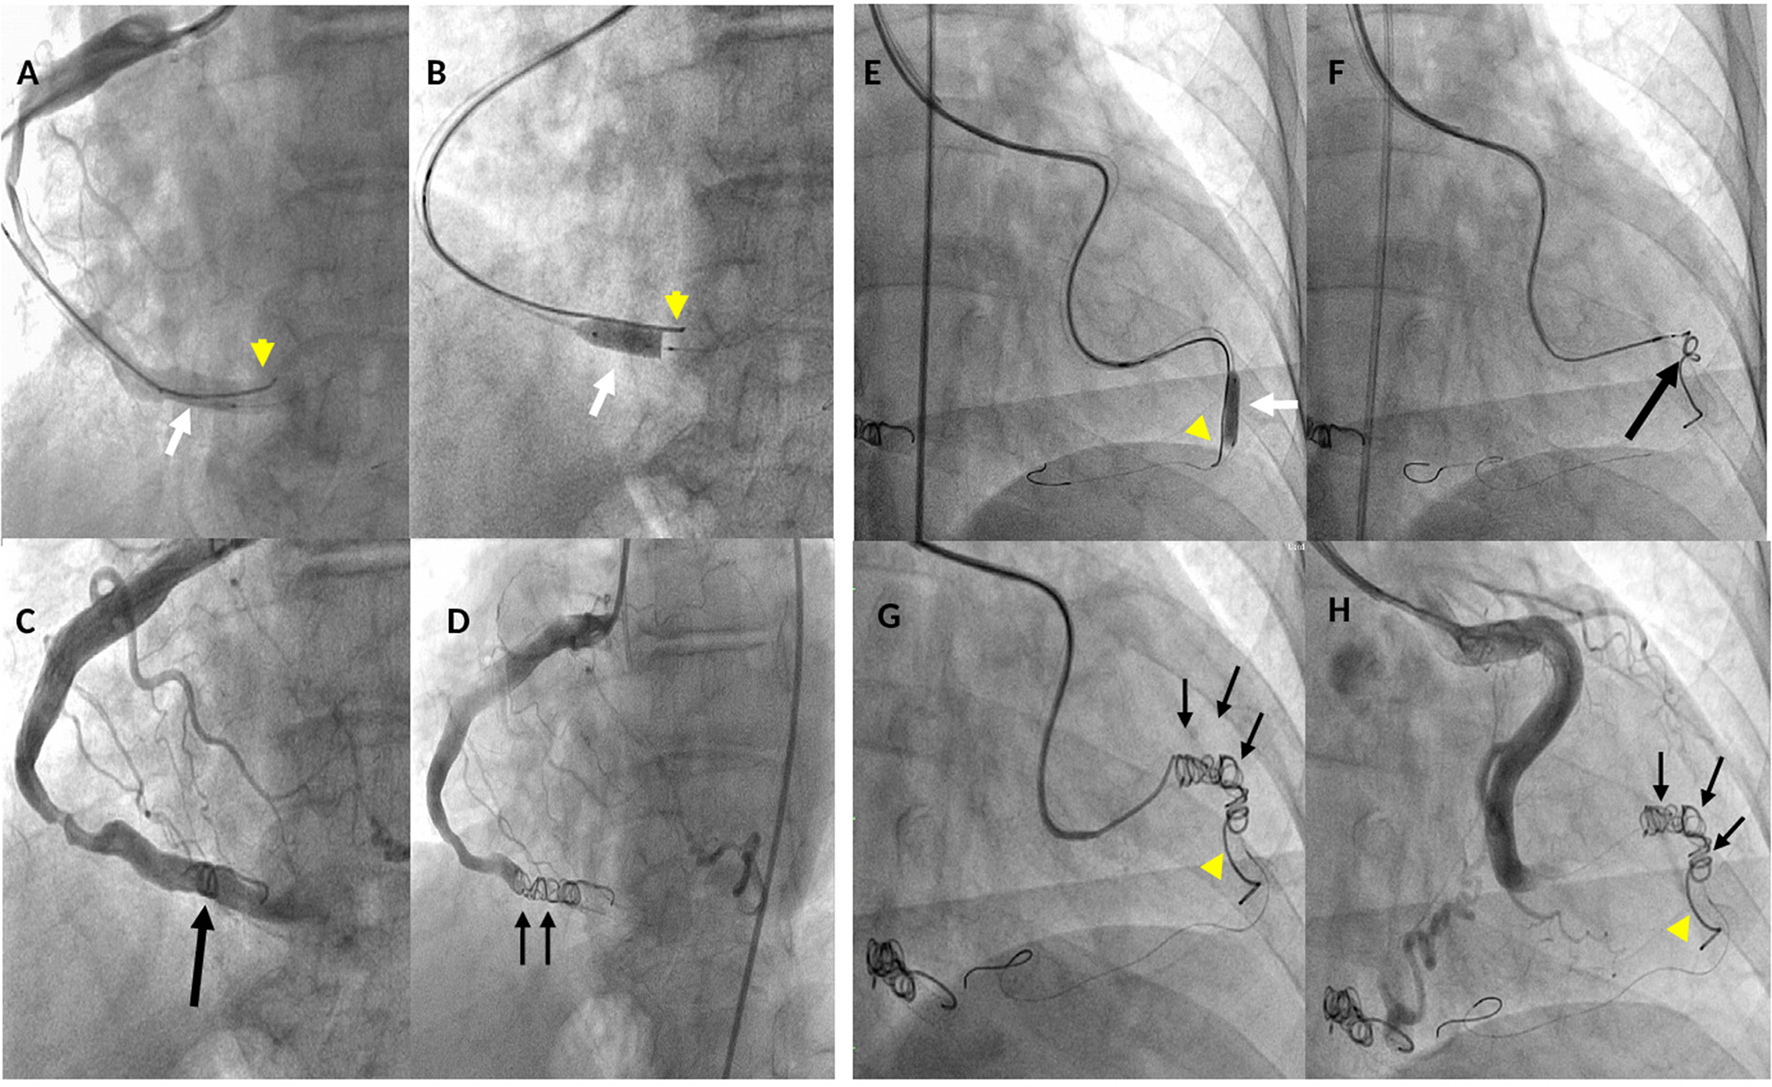

Figure 4

Fluoro-angiographic procedural steps of the coil occlusion of the right coronary (LAO 30° - caud 8°) and left circumflex (RAO 6° - caud 1°) coronary cameral fistulas. (A) through a 6-Fr guiding catheter, a Medtronic Resolute Onyx™ DES 5 × 15 mm (white arrow) and the Cook Mreye(r) Flipper coil 40 × 5 mm through 6-Fr multipurpose catheter with stylet inside (yellow arrowhead) are concomitantly in place in the distal segment of the right coronary artery (RCA); (B) Resolute Onyx™ DES opened and the Cook Flipper coil pinned down by the stent (yellow arrowhead); (C) the Flipper coil is detached and pushed ahead to the stent (black arrow) but still there is residual coronary blood flow; (D) two additional 8 cm × 5 mm Gianturco coils (black small arrows) deployed proximally to the Flipper coil achieving complete occlusion of the fistula; (E) through a Cordis extra back-up (XB) 3.5 guiding catheter, Resolute Onyx™ DES 4.0 × 18 mm was opened (white arrow) pinning down the Cook Mreye(r) Flipper coil (yellow arrowhead) delivered through 5-Fr Cobra C1 with stylet inside; (F) balloon of stent withdrawn, 0.014 inch coronary wire in the distal LCx, Flipper's stylet withdrawn and the Flipper coil pushed distally near the stent; (G) two additional Gianturco coils (10 cm × 5 mm + 8 cm × 5 mm) deployed proximally to the Flipper with effective closure; (H) final left coronary angiogram showing abolition of the coronary flow in the distal segment of the LCx by the implanted coils. LAO, left anterior oblique; RAO, right anterior oblique.

The patient underwent cardiac catheterization and selective coronary artery angiography in multiple projections showing severely dilated and tortuous RCA and LCx draining distally in a large round-shaped chamber within the RV (Figure 3, Supplementary Videos 2, 3) confirming the diagnosis of two CCFs connecting to the RV. After the heart team discussion, the decision to proceed with a catheter-based treatment was confirmed to solve the tricuspid flow compression and prevent fistula-related complications, particularly rupture or endoarteritis. Written informed consent, after explanation, was obtained from the patient. Under mild sedation, 2D TEE color Doppler guidance, and local anesthesia, both radial arteries and the right femoral artery were cannulated. We elected to close the large fistulas via a direct arterial approach with a new stent-assisted coil occlusion technique to avoid the risk of embolization. The RCA was cannulated using a 6-Fr Judkins Right 4 guiding catheter and a 0.014 in Fielder guidewire (Abbott Vascular) was advanced distally and over it, a Medtronic Resolute Onyx™ DES 5 × 15 mm (Medtronic)was placed in the target point (third segment of RCA); concomitantly, a Cook Mreye (r) Flipper coil 40 × 5 mm through 6-Fr multipurpose catheter with stylet inside was placed distally to Onyx™ stent not taking out the stylet from the Flipper to prevent coiling. Then, the balloon of the stent was inflated and the stylet was pulled out from the Mreye (r) Flipper system, getting the system more stable and preventing the stent deformation. The Flipper coil was fixed to the arterial wall, the balloon of the stent deflated and taken out and finally, the coil was pushed ahead and detached. Due to the persistent coronary blood flow across the first implanted coil, two additional 8 cm × 5 mm Gianturco coils were deployed proximally to the Flipper coil achieving complete occlusion of the fistula without compromising the flow in coronary side branches (Figures 4A–D, Supplementary Figure 2). Likewise, the left coronary artery was cannulated using a 5-Fr through a Cordis extra back-up (XB) 3.5 guiding catheter (Cordis) and a Resolute Onyx™ DES 4.0 × 18 mm was implanted in the target point (mid-segment of LCx) pinning down the Cook Mreye ® Flipper coil delivered through 5-Fr Cobra C1 with stylet inside. Subsequently, keeping the 0.014 in Fielder guidewire in the distal segment and withdrawing the balloon of the stent, Flipper's stylet was withdrawn and the Flipper coil pushed distally near the stent. Two additional Gianturco coils (10 cm × 5 mm + 8 cm × 5 mm) were deployed proximally to the Flipper coil. Postprocedure left coronary angiogram showed abolition of the coronary flow by the implanted coils (Figures 4E–H, Supplementary Figure 2).